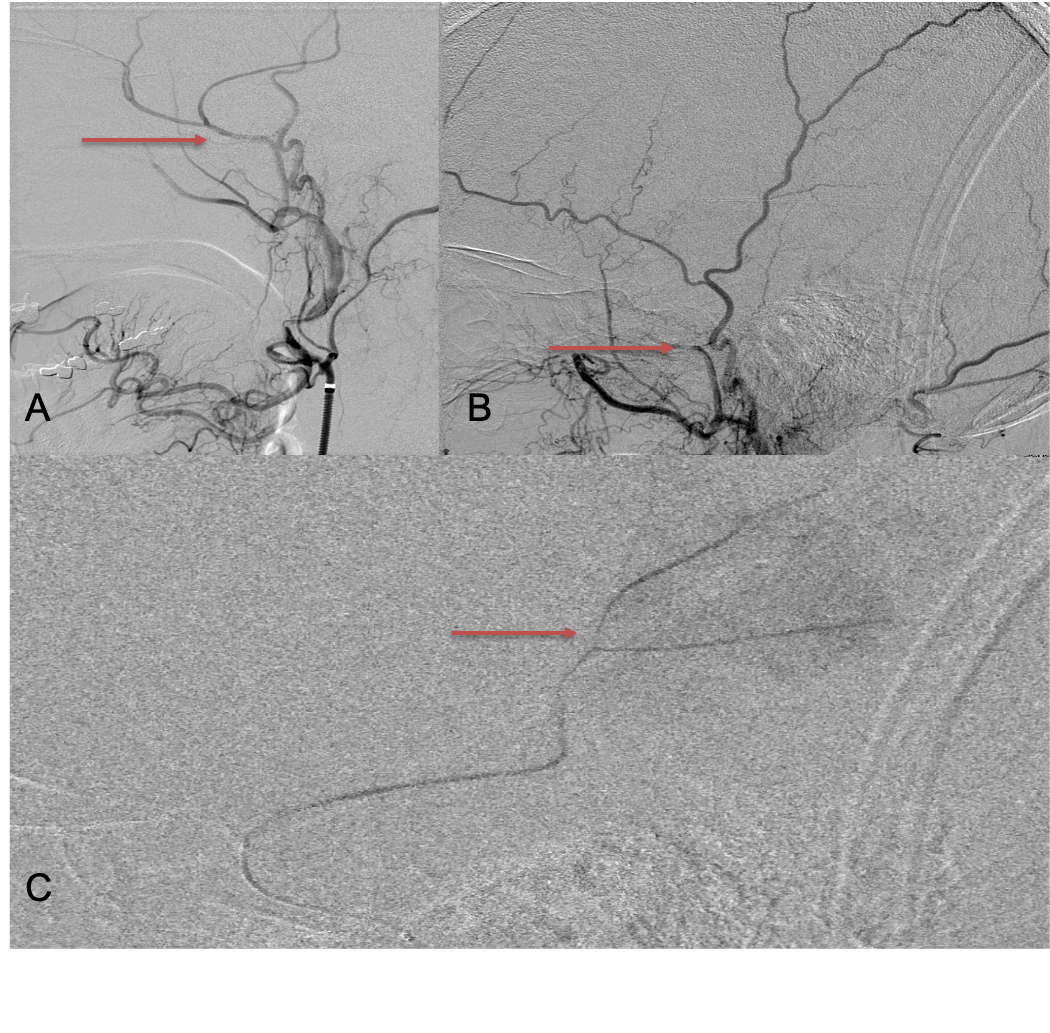

CT follow-up at 1 week demonstrates early resorption. 2 weeks post MMA embolization, resolution of the left subdural collection with new small thin acute hemorrhage in an otherwise stable right subdural collection is observed (Figure 3. A and B).

Figure 3. A) 1 week post MMA embolization demonstrating decreasing thickness bilaterally B) 2 weeks post MMA demonstrates resolution on left, with small new acute component on right with overall decreased thickness.

Clinically, the patient improved over the few weeks with the occasional transient twinge of a headache, but resolution of dizziness. Follow-up CT at 10 weeks demonstrated complete resolution of the bilateral subdural hematomas with our patient complete symptomatic and back to all of his activities of daily living. Considering his history of thrombocytopenia and CLL, we will continue to monitor him into the future and are excited about his progress and recovery. (Figure 4. A and B)

Figure 4. A and B) – 10 weeks following embolization demonstrates complete resolution of bilateral collections both acute and chronic.